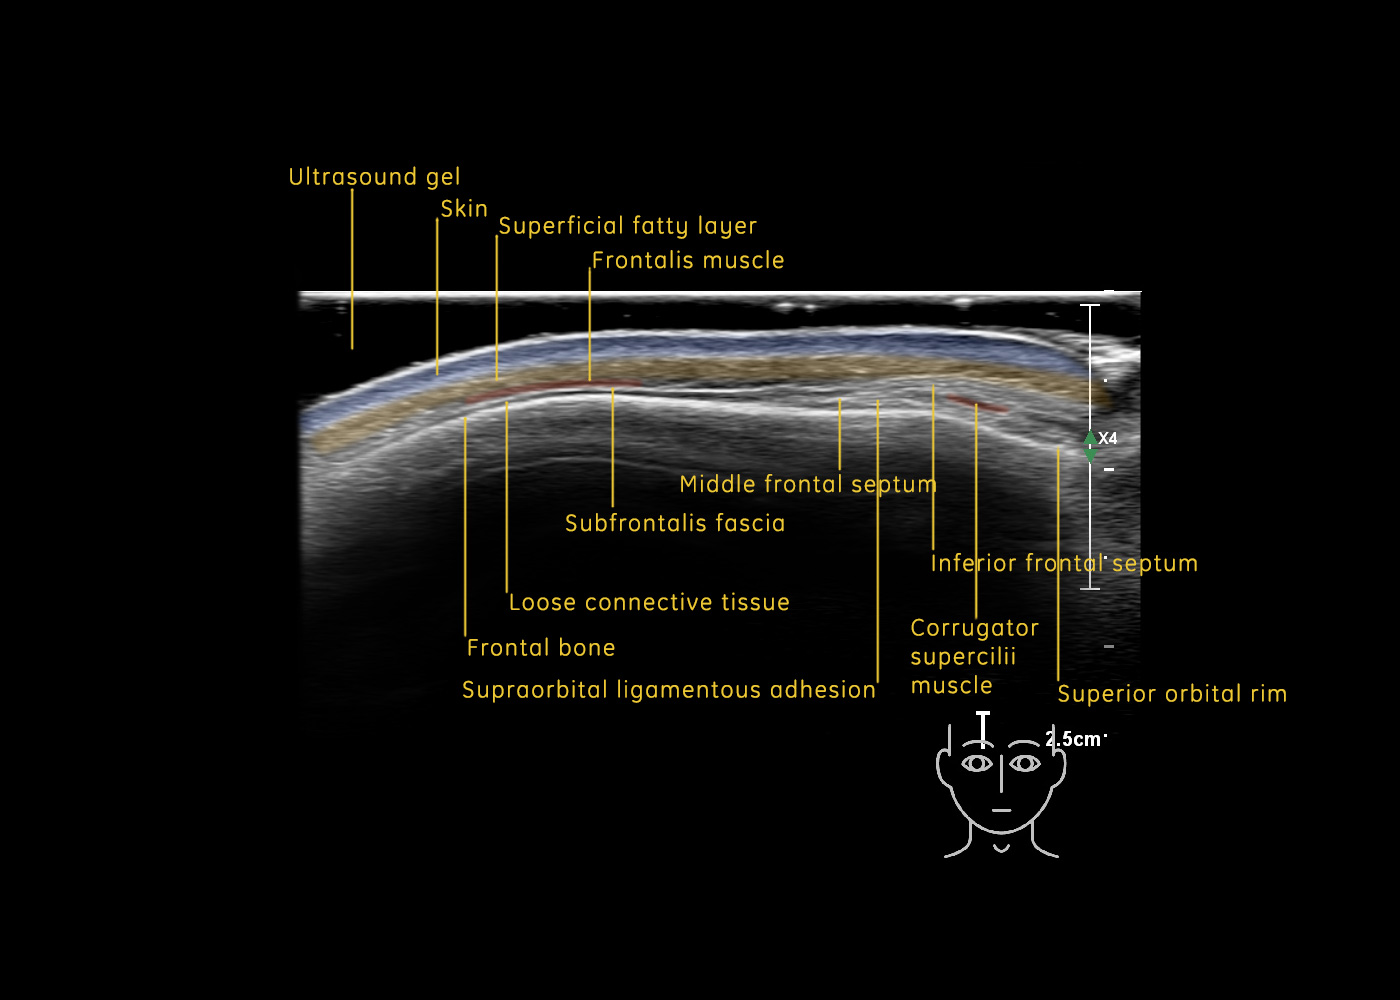

In this section you will learn more about the different layers of the face with the use of ultrasound. When you click on the secondary ultrasound image, you will see the different structures as an overlay. This will help to train yourself to recognize the different layers of the face.

Study the first image to recognize the different layers. If you are sure about the layers, swipe to the second image to view the answer (if applicable).